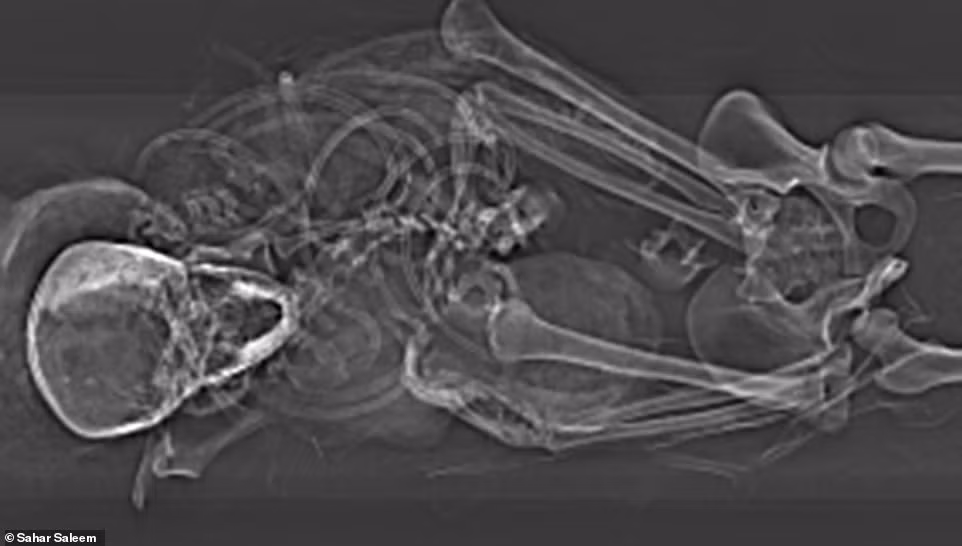

Thông qua phương pháp chụp cắt lớp vi tính (chụp CT) xác ướp, giới chuyên gia phát hiện ông hoàng này có cái chết thảm khốc và đau đớn.

Cụ thể, kết quả chụp CT cho thấy phần mặt của xác ướp có nhiều vết thương. Những người thợ ướp xác cố gắng che những vết thương này khi bảo quản thi hài nhà vua.

Vào thời điểm qua đời, pharaoh Seqenenre Taa II có một vết thương lớn trên trán, vết cắt xung quanh mắt và má, một vết đâm ở đáy hộp sọ. Hộp sọ của nhà vua tách rời khỏi phần còn lại của thi hài.

Với những vết thương này, các chuyên gia nhận định pharaoh Seqenenre Taa II bị kẻ thù bao vây và tấn công từ nhiều phía. Họ sử dụng dao găm, rìu và giáo tấn công nhà vua Ai Cập đến chết.

Hai tay của pharaoh Seqenenre Taa II không có vết thương nào và ở trong trạng thái nắm chặt. Từ đây, các chuyên gia suy đoán ông bị trói chặt 2 tay khi bị kẻ thù sát hại.